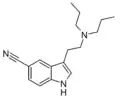

| 5-CN-DPT | artificial | 5-C≡N | CH2CH2CH3 | CH2CH2CH3 | 5-cyano-N,N-dipropyltryptamine | 74885-19-1 |